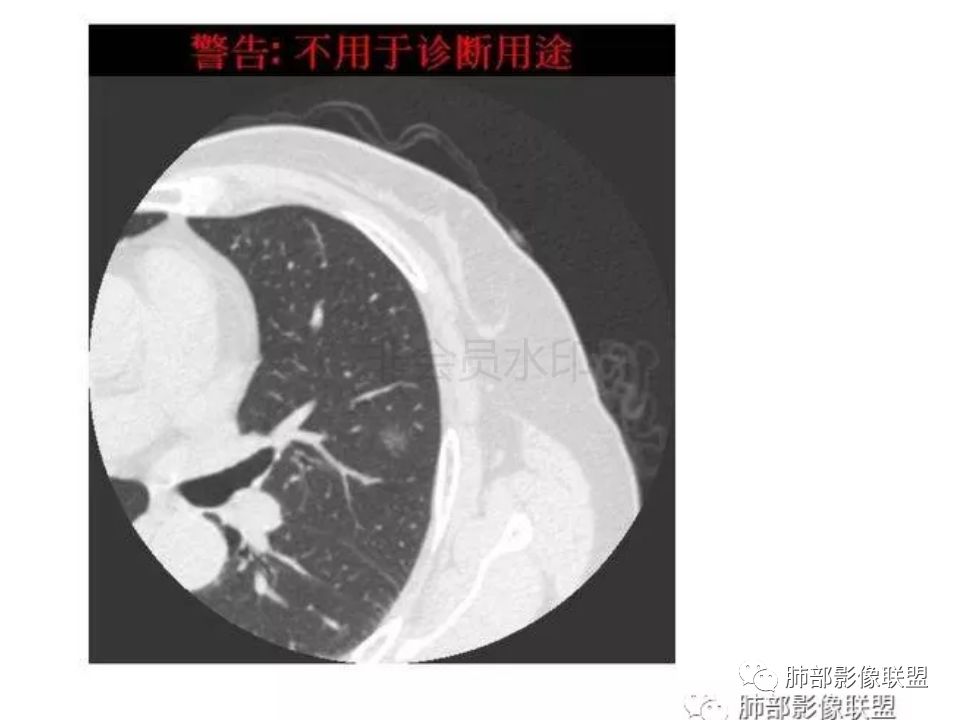

三生石上:支气管有截断,周围有晕,有空泡,腺癌?毛勤香:左肺下叶近胸膜下结节,周围磨玻璃影,边界似稍模糊,局部细支气管截断,实性区和磨玻璃区分界突然,隐约细毛刺,首先考虑感染性,隐球菌?待排腺癌MIA伴肺泡塌陷可能。常规治疗后复查。Coke with ice:IACM-Imaging :孤立胸膜下结节,其内见小泡,周围模糊的晕,晕中软毛刺,近端与血管相连,血管自然通过,气管进入结节内部一半,猜个隐球吧。第二腺癌,建议复查。田园晚风:考虑腺癌紫气东来:左肺上叶,磨玻璃实性毛刺,空泡,支气管截断,腺癌雪颜:左肺上叶结节状密度增高影,周围有晕,感觉周围模糊,有血管进入,里面有空泡征,隐约看到里面有支气管穿过,考虑炎性,隐球菌感染?腺癌待排THINKER:上叶尖后,SPN,有晕,软毛刺,无胸膜凹陷,分叶丶收缩不明显,支气管进入,远端阻塞,首选肉芽肿,PC或炎性结节,有一支血管滋养,鉴别腺癌,增殖性结核结节不支持期:左上肺结节周围有晕 晕中见细软毛刺 首先考虑隐球菌一米阳光:左肺上叶磨玻璃影,空泡,周围毛刺,月牙铲,支气管通过,周围有晕,考虑腺癌我的FY:毛刺,小空泡,磨玻璃考虑恶性崔少钢:小病灶,内有支气管,空泡征,实变不规则,放大了,感觉晕有点偏清,考虑恶性。小病灶里面有支气管是值得高度怀疑的。没有病史。彭君:左肺上叶舌段结节 周围晕模糊 内小支气管扩张 近端与血管相连 自然通过 首先考虑炎性 隐球菌?边缘月牙铲 腺癌待鉴别徐婕:左上肺结节周围有晕 ,晕中见细软毛刺 ,晕边界不太清,先考虑隐球菌张帅:左肺上叶尖后段实性病灶,以细支气管为中心,周围呈毛玻璃样影,并可见密集分布毛刺,内可见支气管征,支气管呈壁呈结节样改变,病灶周围可见血管增粗。考虑 淋巴瘤?鉴别隐球。张延军:混合型磨玻璃结节,伴毛刺,支气管截断,空泡,考虑浸润性腺癌,建议抗炎治疗后复查XGQ:支持隐球春秋:结节伴晕征,晕中毛刺,相邻小支气管近端进入,远端阻塞,近端血管相连,首先考虑隐球菌王秀仙:左肺上叶混合型磨玻璃结节,支气管截断,空泡,有毛刺,考虑浸润性腺癌,建议抗炎治疗后复查玫:左肺上叶磨玻璃结节影,薄扫见长短不一毛刺,有空泡,病灶边缘见晕征,考虑小腺癌可能,不除外炎性结节。zyf:左肺下叶近胸膜下结节,周围有晕,细软毛刺,有支气管进入,实性区和磨玻璃区分界明显,首先考虑感染性,隐球菌?查隐球菌荚膜抗原!RockJ-ason:考虑隐球采莲:左上肺靠近胸膜下实性结节影,边缘模糊,周围有晕及晕中毛刺,支气管进入通畅,有小空泡。考虑炎性病变,隐球可能性大。鉴别结核。Harvey:左肺下叶舌部小结节,边缘见磨玻璃影,边界欠清,内见支气管、管壁不光整,偏向恶性。鉴别隐球菌lmg:左肺上叶混合小结节,有晕,边界模糊,有有小毛刺。考虑炎性病变,隐球收选。AIS并肺泡塌陷带排。山河:倾向腺癌红日东升:GGO边界似清非清,内部好像不是小空泡,是小支气管腔,倾向炎性病变,常规抗炎复查除外腺癌,尤其粘液腺癌。

我怎么感觉支气管是通的,周围的晕又比较软,我考虑炎性病变,隐球菌可能大(如下图)

隐球菌感染孤立病灶与肺腺癌结节在影像上有时难分彼此,尽管隐球菌胸膜下更常见。

1.隐球菌病灶往往是实性密度结节为主伴周边边界不清楚的晕,有时可见晕内细软毛刺。

2.隐球菌病灶形态往往圆钝柔和,缺乏收缩能力,很少出现腺癌的那种胸膜牵拉和棘状突起。

3.病灶内支气管安然无恙隐球菌病灶更加多见